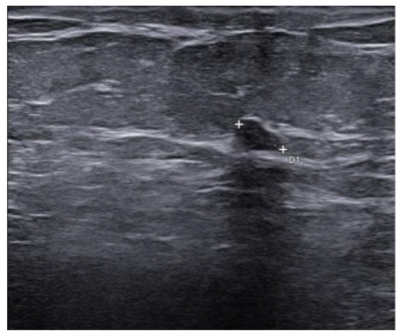

In September 2019, a 69-year-old woman presented to the emergency department of the University Hospital Città della Salute e della Scienza – Turin (Italy), reporting extreme fatigue and dyspnea. She had no comorbidities except for a medical history of papillary thyroid cancer, treated with thyroidectomy and radiotherapy 13 years before. Her complete blood count revealed anemia, thrombocytopenia and leukocytosis (Hb: 7.8 g/dL, PLT: 37 × 109/L, WBC: 45 × 109/L), while her physical examination was normal. The bone marrow smear showed 84% of blasts with myeloid immunophenotype (CD45, CD13, CD33, HLA-DR, lysozyme, CD36, CD64, CD11bc, partial CD14, and CD4 positive), molecular biology showed NPM1 mutation and FLT3-ITD positivity, while karyotype was normal (46, XX, 20/20). Consequently, a diagnosis of FLT3-ITD+ and NPM1 mutated t-AML was made. Induction chemotherapy was started with CPX-351 (liposomal daunorubicin 44 mg/m2 and cytarabine 100 mg/m2), obtaining CR with a 3-log NPM1 reduction (0.177). She was consolidated with CPX-351 (liposomal daunorubicin 29 mg/m2 and cytarabine 65 mg/m2 day 1 and 3), remaining in CR with persistent low level of measurable residual disease (MRD), NPM1 0.34. Meanwhile, we found a suitable HLA matched donor, but the patient refused the transplant procedure. Thus, we decided to start off-label azacitidine as maintenance therapy (50 mg/m2 subcutaneous daily for 5 days, every 28 days). Maintenance therapy was globally well tolerated, and the patient experienced only positivity for COVID-19 without need of hospitalization or additional care. She remained in CR with persistent MRD in BM (NPM1 0.044 after 12 cycles). During the fifteen course (May 2021), we found a palpable right mammary nodule on physical examination, confirmed on ultrasound, with a diameter of 18 x 11 mm. We stopped azacitidine and we promptly biopsied the nodule with a diagnosis of breast infiltration by AML blasts carrying the NPM1 mutation. CT scan and PET of chest, neck and abdomen were negative, and BM evaluation showed 1% blasts, with NPM1 0.044. The FLT3-ITD mutation resulted positive on breast cells while negative on medullary blasts. Thus, concluding for extramedullary relapse of AML FLT3-ITD mutated, we decided to start gilteritinib as single agent, at a dose of 120 mg daily. After 30 days, mammary ultrasound showed a reduction in diameter of the nodule, and in 4 months, the lesion has completely disappeared. The PET scan performed after 5 months of treatment was persistently negative and confirmed the absence of other uptakes. BM re-evaluation showed no blasts, with NPM1 0.006. Today, after 44 months of treatment, our patient is still in CR without signs of clinical and radiologic relapse. We continue monitoring her MRD status every two months on peripheral blood, as shown in table 1. Globally, therapy has been always well tolerated. In January 2024, we had to stop gilteritinib for 28 days due to pyelonephritis and sepsis treated with broad spectrum antibiotics. During this time, she remained in complete remission without any sign of relapse. After some months, in September, our patient has undergone exeresis of basal cell carcinoma, without complications and without need of stopping gilteritinib.